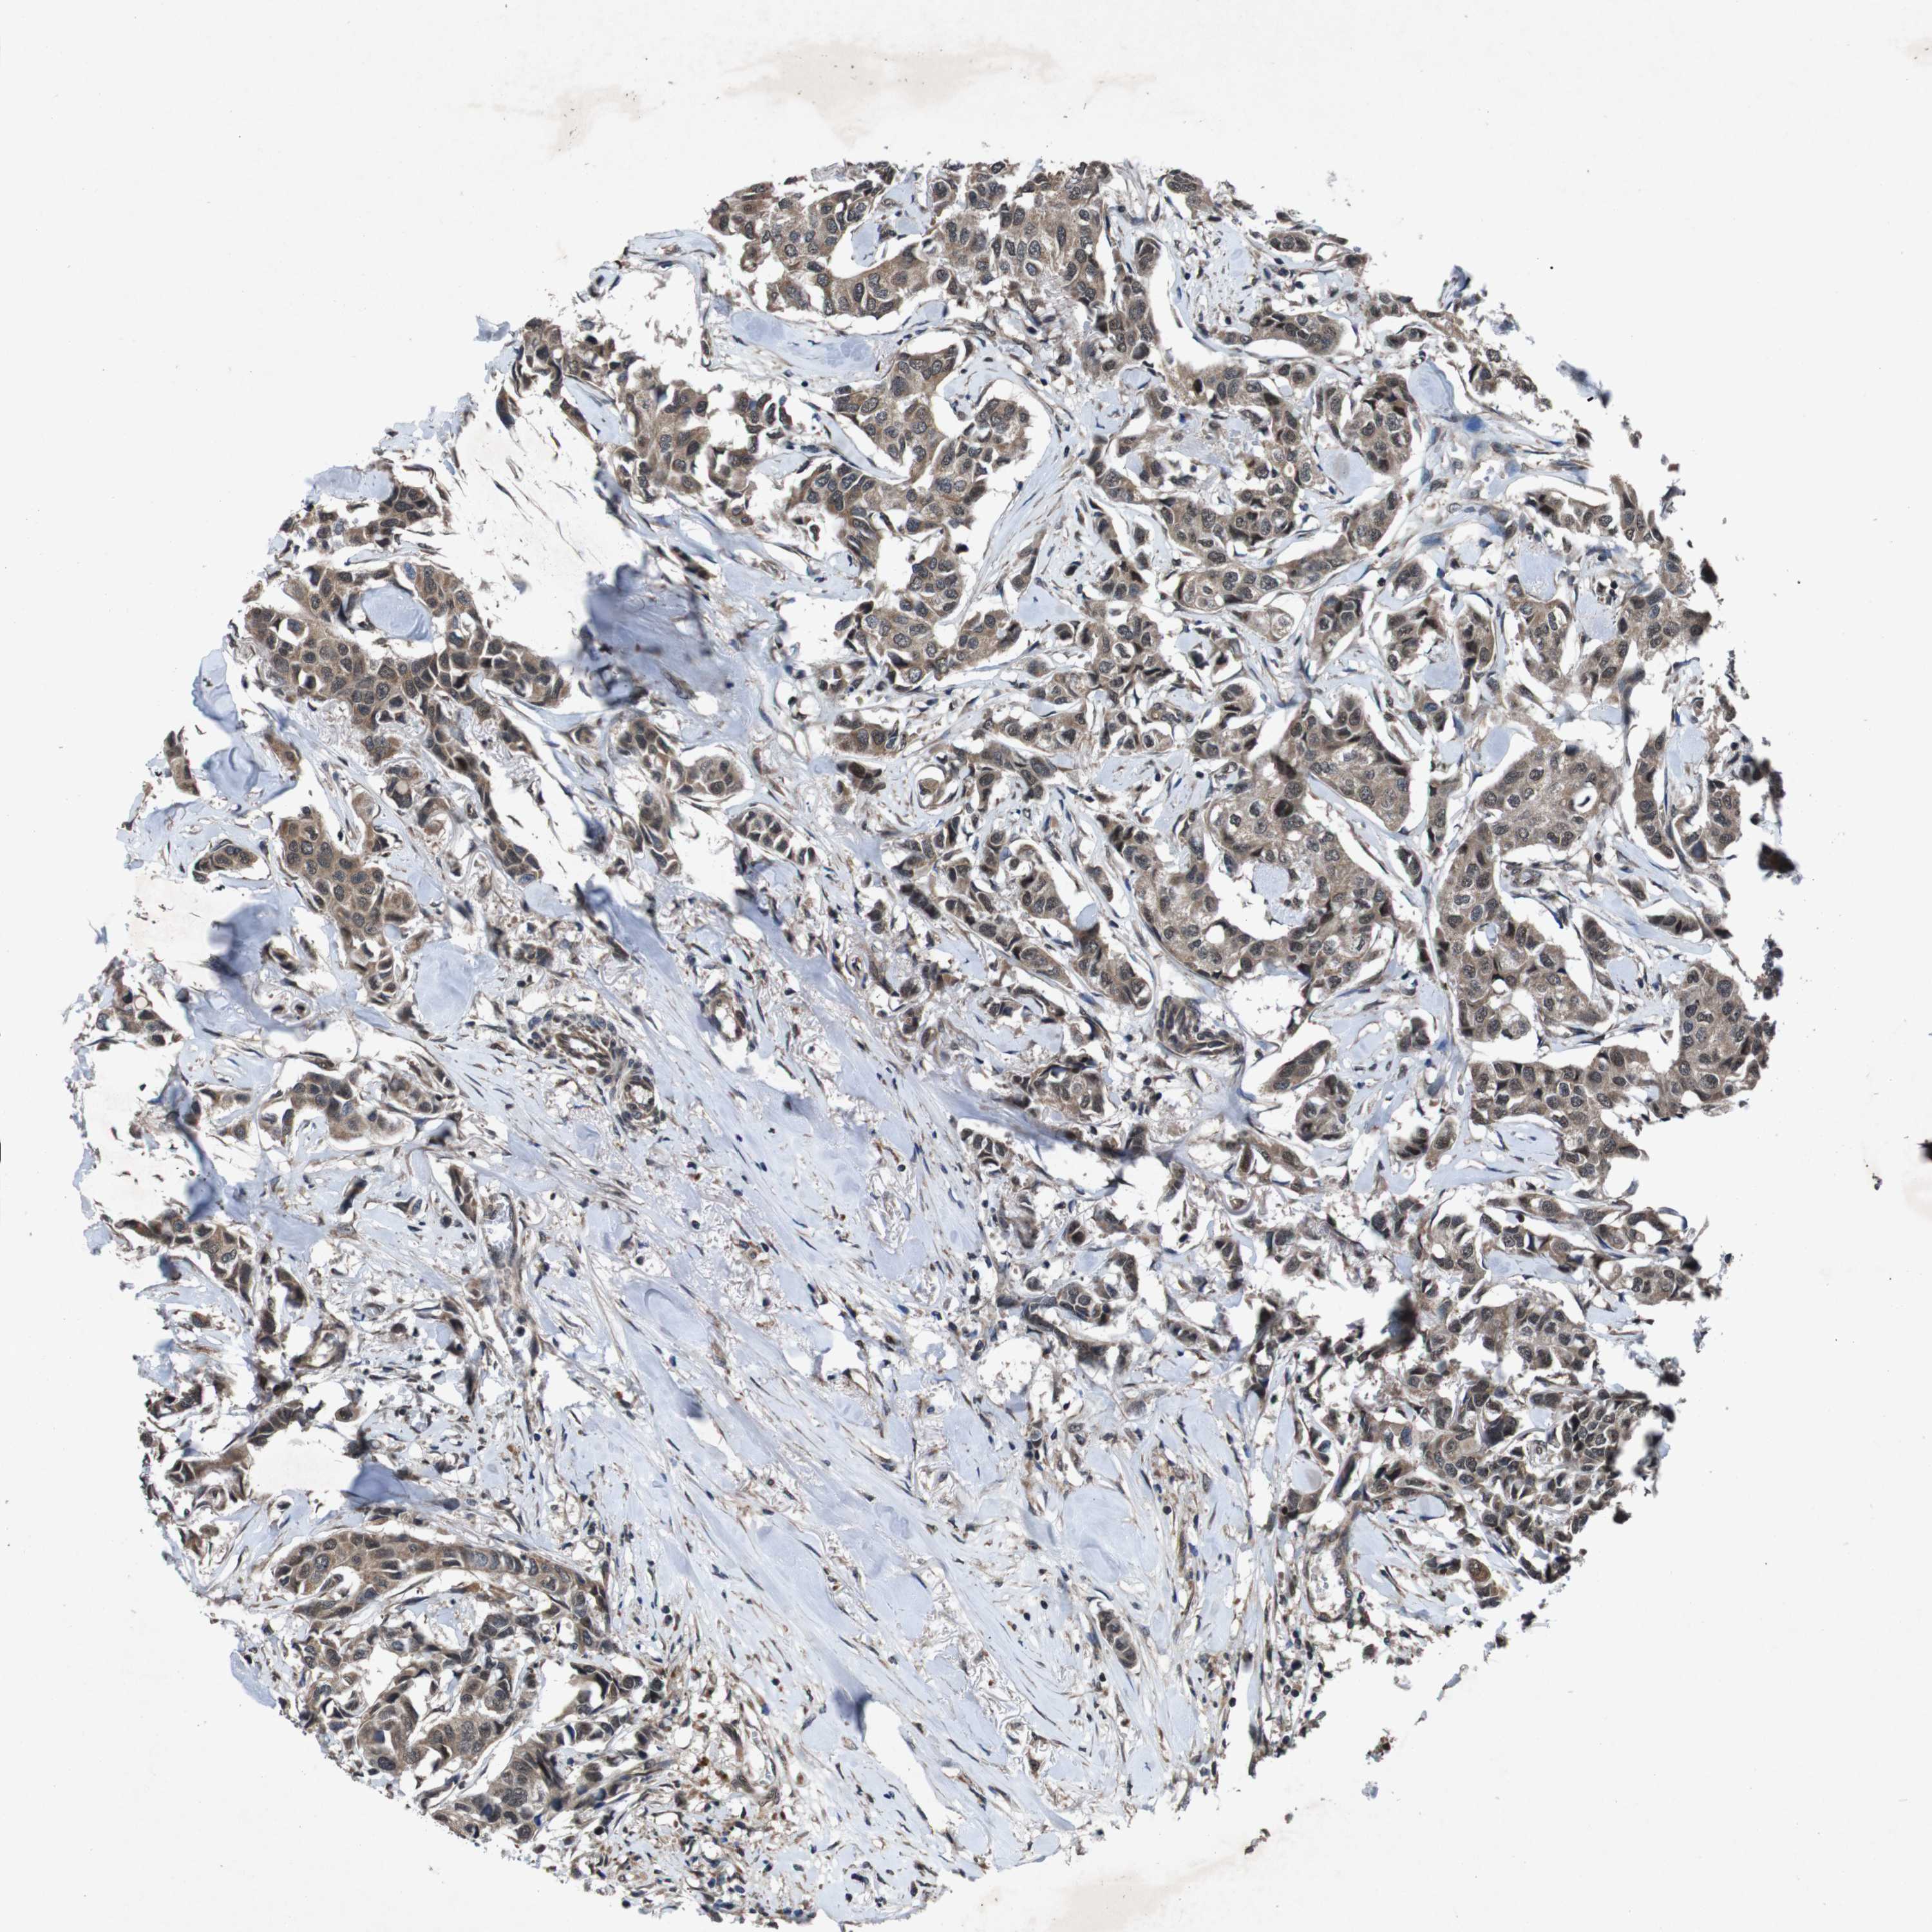

BRCA TCGA BRCA VALIDATION PROTEIN EXPRESSION

ANTIBODIES

AND

VALIDATION